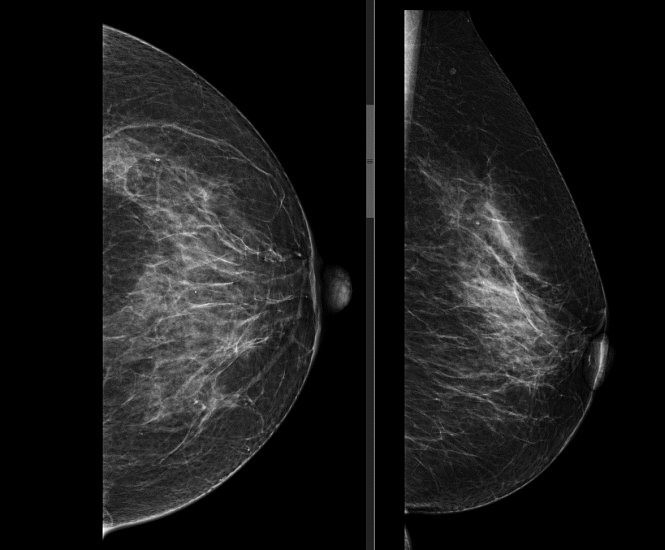

Маммография – это тип специального медицинского обследования, которое проводится с применением системы рентгена с малыми дозами облучения для исследования груди женщины (и мужчины - по показаниям).

Аппарат, на котором врач проводит данное исследование, называется — маммограф. Исследование на нем позволяет выявить болезни молочных желез на ранних стадиях, в том числе и такие опасные, как рак молочных желез.

Исследование проводится стоя, предварительно сняв верхнюю и нижнюю одежду области исследования, а также все украшения в области зоны интереса. Для получения четких и подробных снимков, молочную железу располагают между двух пластин маммографа, которые слегка сдавливая, фиксируют ее в неподвижном положении, добиваясь равномерного распределения тканей. Затем специалист делает снимок молочной железы в боковой и прямой проекции. Исследуются поочередно обе груди.